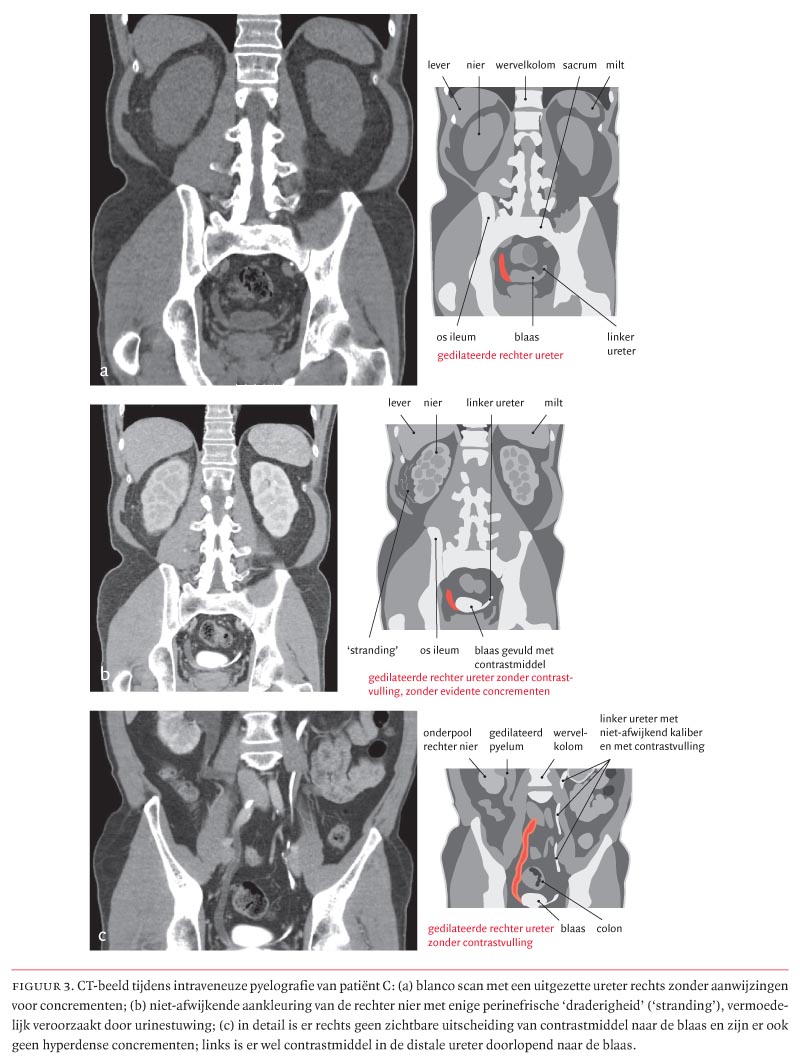

In het artikel van Brandenburg et al. getiteld ‘Drie patiënten met urolithiasis als bijwerking van behandeling met indinavir’ (2007:1839-45) zijn in 2 figuren fouten geslopen: op bl. 1841 dient in de verklarende tekening bij figuur 2b in plaats van ‘pyelum met contrastmiddel’ te worden gelezen ‘kelk met contrastmiddel’ en in plaats van ‘nefrostomiekatheter’ ‘punctienaald’. In figuur 3 op bl. 1843 staan de verklarende tekeningen op een verwarrende plaats en ze zijn hier en daar onjuist. Een verbeterde versie van de figuur staat op bl. 2076.